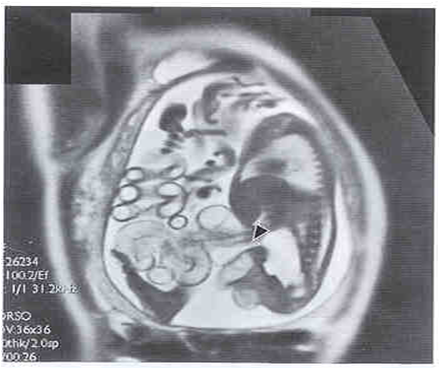

【产前诊断(Prenatal diagnosis)】

胎儿超声与MRI:可见胎儿胸腔内有腹部脏器

胸腹部正侧位摄片:

◇ 可见患侧胸腔内有典型的充气胃和肠曲,并向腹部延续现象。

◇ 病变侧看不到正常膈肌 形态。

◇ 腹部气体影减少。